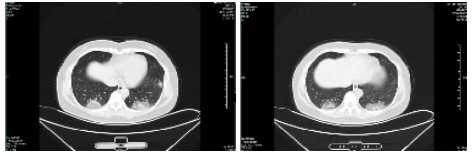

| 图 2 患者,女性,64岁,武汉籍,发病前1 d由武汉自驾车入沪,出现发热,体温39.9℃, 伴全身乏力,无咳嗽症状,无鼻塞,流涕症状,血白细胞总数及淋巴计数正常,甲乙型流感病毒筛查阴性,新型冠状病毒核酸检测阳性,肺部CT双肺多发磨玻璃结节,部分贴近胸膜,左肺有少量胸腔积液,局部小叶间隔增厚, 可见纤维条索影 Fig 2 Case 2, female, 64 years old, born in Wuhan. One day before the onset of the disease, she drove into Shanghai from Wuhan and had fever. Her body temperature was 39.9℃, with general asthenia, no cough, no nasal obstruction and running nose, normal WBC and lymphoid count, negative influenza A and B virus screening, positive novel coronavirus nucleic acid test. Lung CT showed multiple ground glass nodules, some of which were close to pleura, a small amount of pleural effusion in the left lung, and local interlobular septa was thickened, with visible fibrous streak shadow |

| 图 3 患者,女性,49岁,沪籍,发热10 d,体温最高38.5℃,伴乏力,肌肉酸痛,既往体健。否认武汉流行病学接触史,有菜场买菜史。血白细胞总数及淋巴计数正常,甲型、乙型流感筛查阴性,新型冠状病毒核酸检测阳性。肺部CT提示双肺磨玻璃结节,可见血管充血,增粗,穿行,部分贴近胸膜,伴小叶间隔增厚 Fig 3 Case 3, female, 49 years old, born in Shanghai, had fever for 10 days, body temperature 38.5℃, with fatigue, muscle pain, previous physical fitness. She denied the history of epidemic exposure of Wuhan, but had the history of shopping in market. Normal WBC and lymphoid count, negative influenza A and B virus screening, positive novel coronavirus nucleic acid test. Lung CT showed bilateral ground glass nodules with hyperemia, thickening and passage of blood vessels. Some were close to pleura with thickening of interlobular septum |